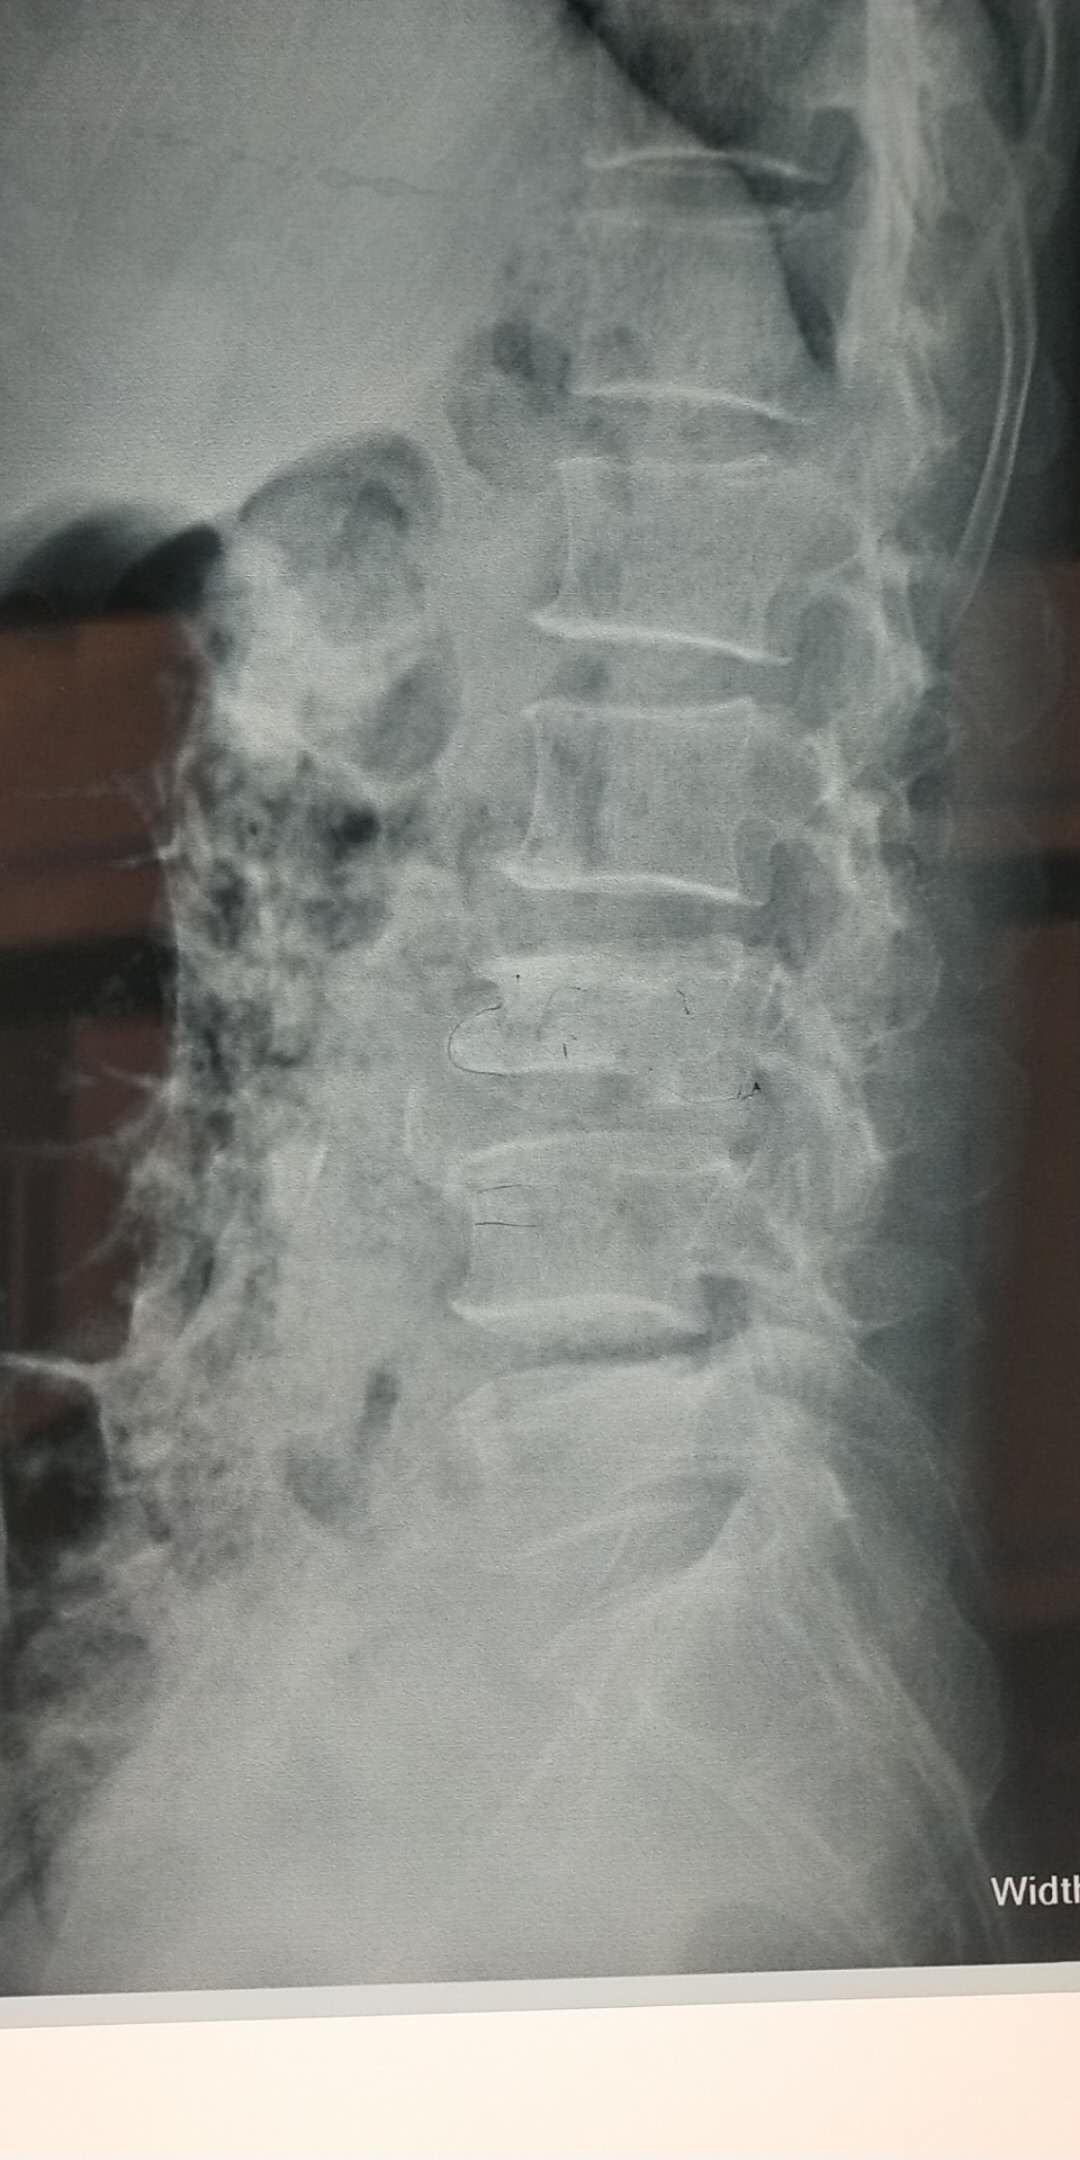

術(shù)前片子

骨一科已成功為數十名患者成功開(kāi)展PVP手術(shù)。僅今年3月份,在何光亮主任的帶領(lǐng)下,骨一科已經(jīng)成功開(kāi)展5例PVP手術(shù),術(shù)后患者相當滿(mǎn)意,全部患者術(shù)后可自行行走,擺脫臥床。3月21日患者王某,90歲,因摔傷致腰部疼痛3天為主訴入院,診斷腰1椎體骨折、骨質(zhì)疏松癥、高血壓等,住院后經(jīng)過(guò)科室術(shù)前討論,何主任為患者制定了PVP手術(shù)方案,于3月22日在行腰1椎體壓縮性骨折經(jīng)皮穿刺椎體成形骨水泥填充術(shù),術(shù)后24小時(shí)患者即下床活動(dòng),術(shù)后一周患者痊愈出院,隨訪(fǎng)患者已基本恢復到術(shù)前狀態(tài)。